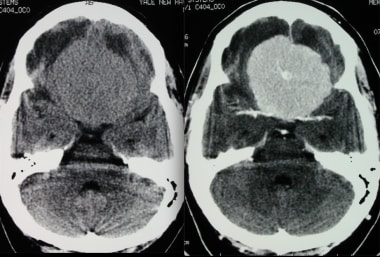

无对比和有对比的横轴位CT显示在这种强烈增强的脑膜瘤内有轮辐状图案。虽然这种模式通常在血管造影中看到,但也可以在横断面成像中注意到。

随后的核磁共振成像显示先前的计算机断层扫描具有以下序列:钆注射后的轴向T1和轴向T2序列。这再次显示了一个较大的中线额骨脑膜瘤,呈轮辐状。